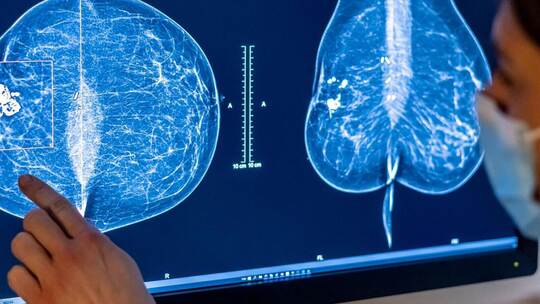

Ofirzheim/Berlin. 38 Prozent aller Krebserkrankungen, also mehr als ein Drittel, gehen auf vermeidbare Ursachen zurück. Das zeigt eine Analyse globaler Daten aus dem Jahr 2022, als weltweit 18,7 Millionen neue Krebserkrankungen erfasst wurden. Als häufigste Ursachen werden Rauchen, Alkoholkonsum und Infektionen genannt. Bei Frauen sind der Analyse zufolge etwa 30 Prozent aller Krebserkrankungen vermeidbar, bei Männern sogar gut 45 Prozent.